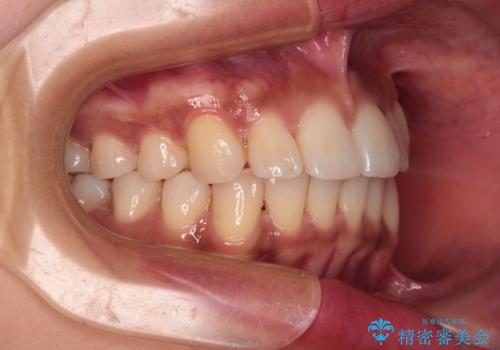

カリエール・ディスタライザーを併用したインビザライン矯正治療

- 全体的な歯列の叢生を気にして来院された患者様です。

奥歯の咬み合わせを見ると、片方は上顎が下顎に対して相対的に前方にある状態でした。

咬み合わせを改善するためには、上顎臼歯を後方に移動させた咬み合わせにする必要があります。

インビザライン単体で改善することも可能ですが、ディープバイトのためインビザライン単体で達成する可能性が低いと考えられたため、カリエール・ディスタライザーという補助装置を併用して、より確実性を上げることとしました。

奥歯の咬み合わせ改善後に、インビザラインにて歯列を整えることとしました。